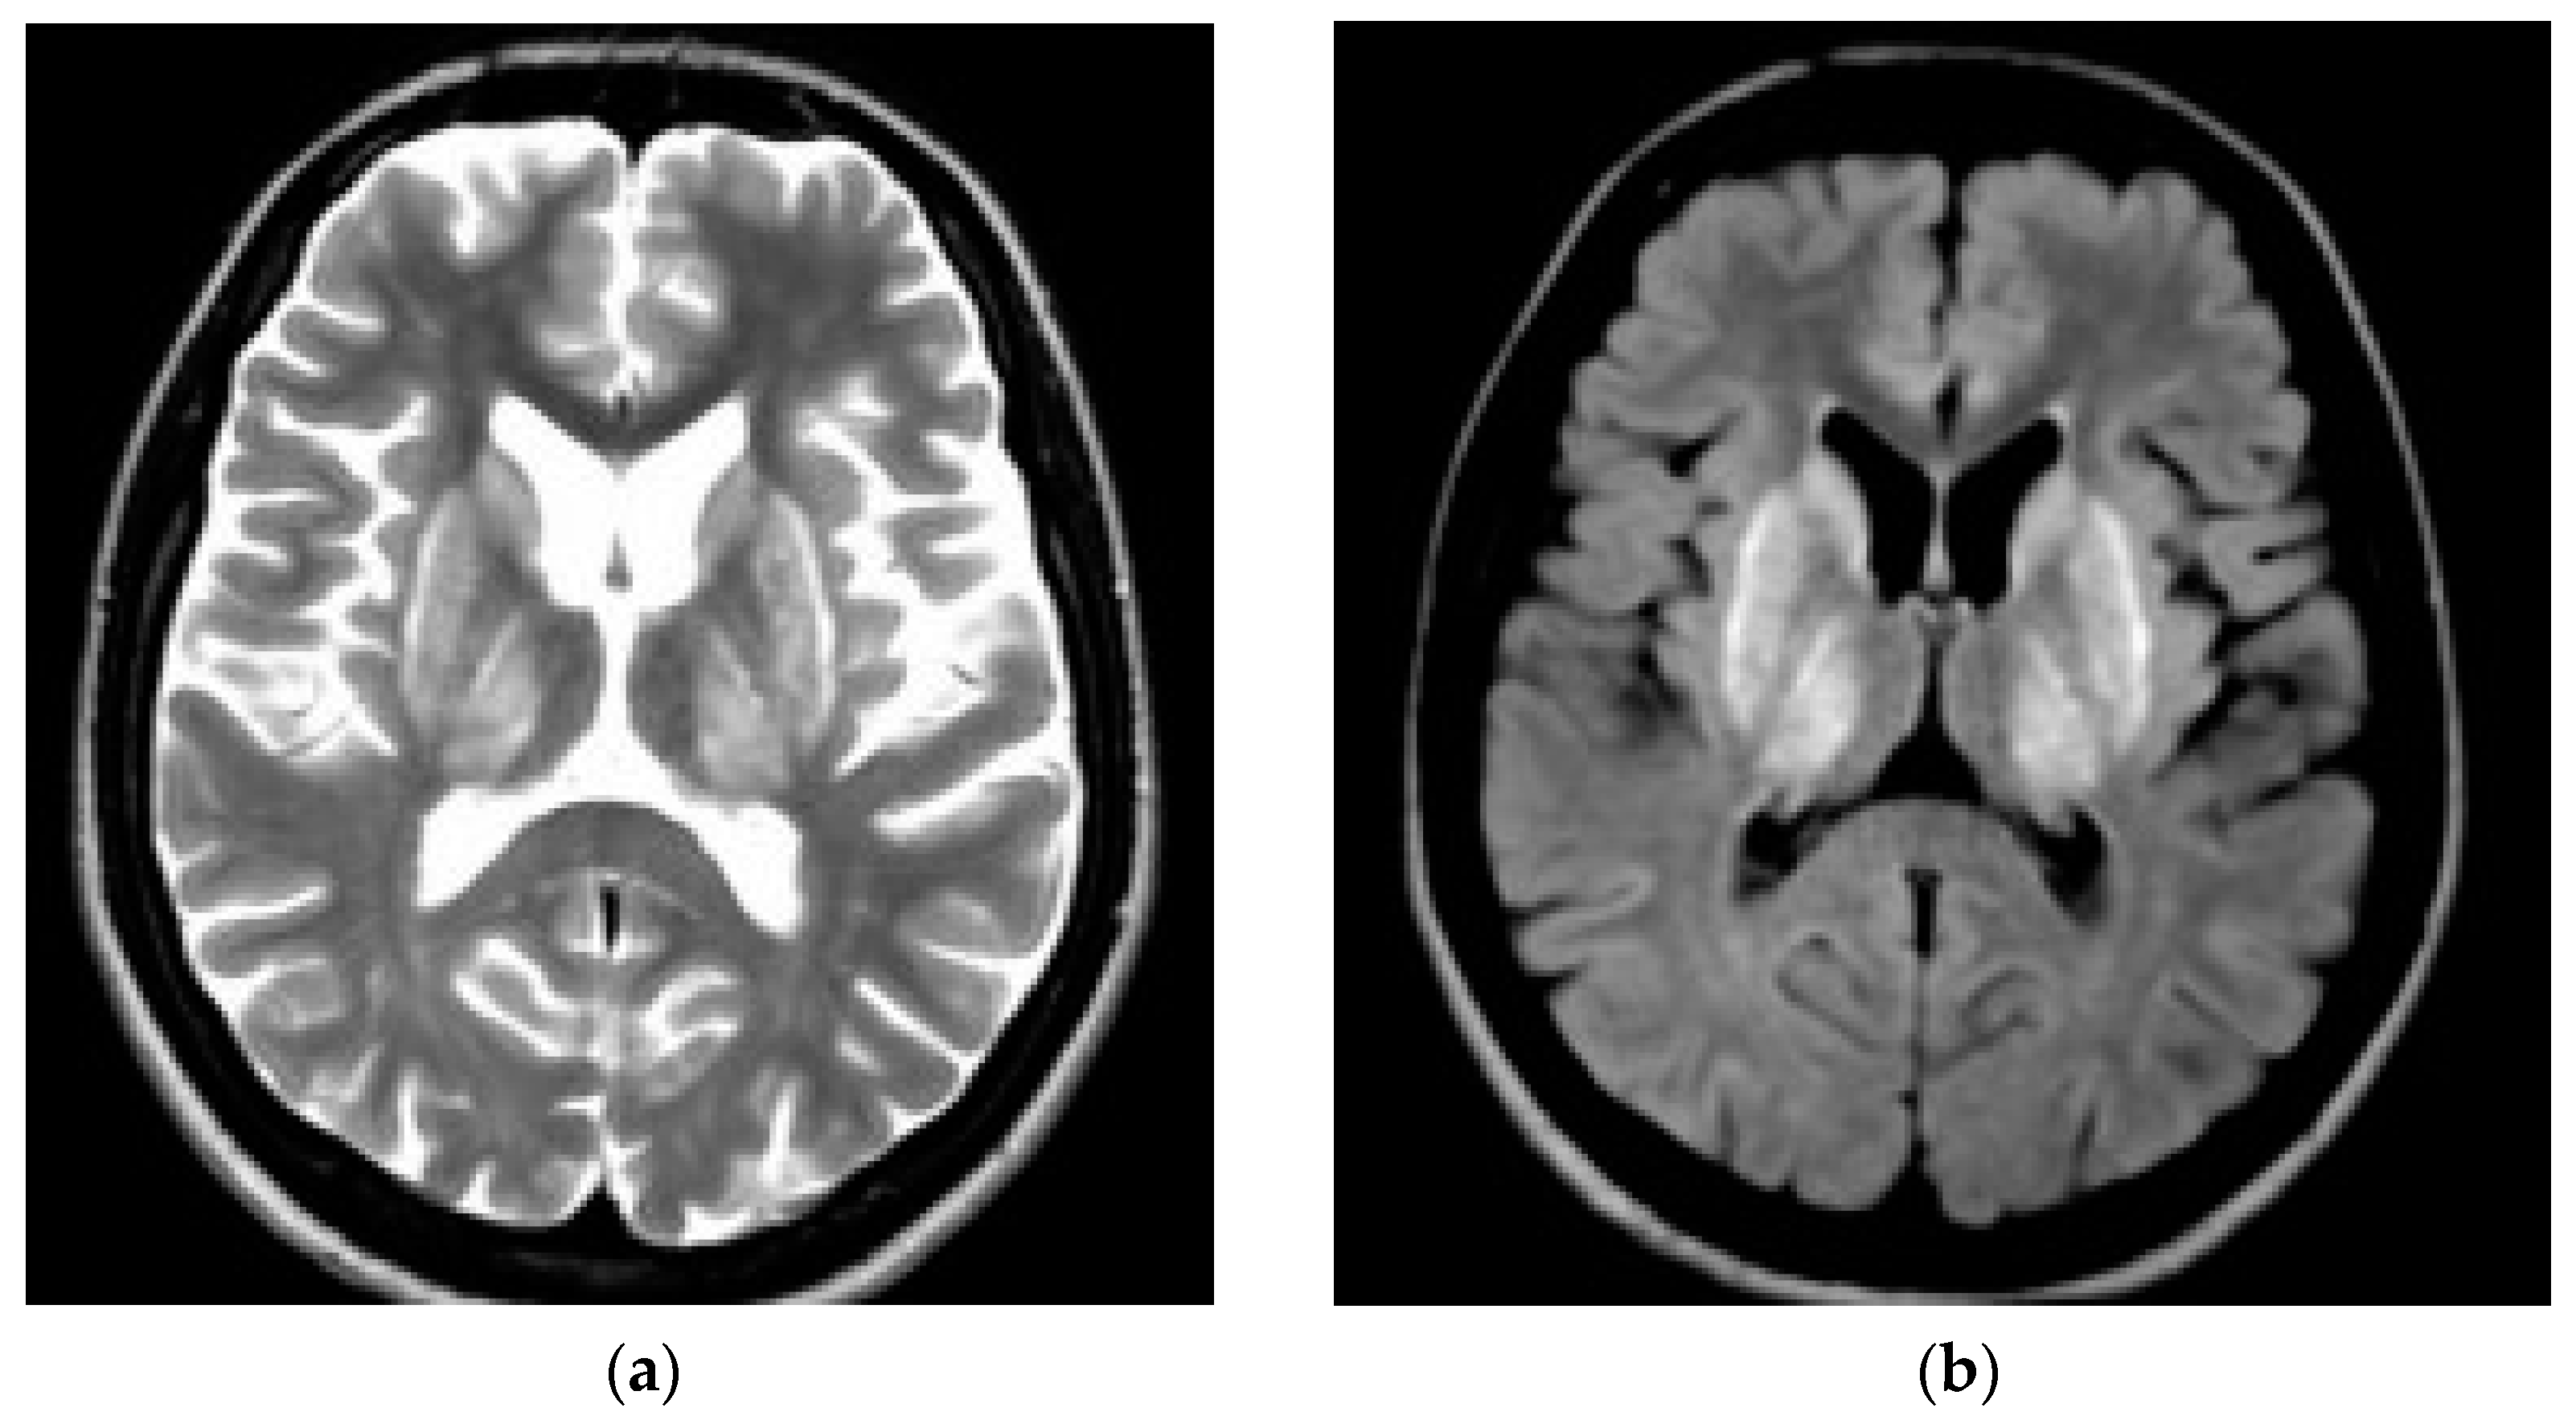

3. CNS Pathology in WD—Neuroimaging Studies